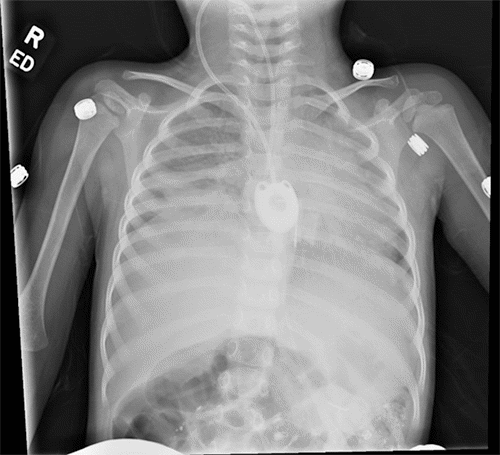

After the procedure, a chest X ray (Figure 1) confirmed the seemingly successful placement of the CVC chemo-port; the patient was transferred to the pediatrics team for postoperative monitoring. Over the next few days, the port never functioned correctly. A minimal amount of blood was able to be aspirated from the port. While it seemed to flush well, the patient would complain of severe pain when normal saline flush was injected through the port. The pain was described as being all over her body. She could not be distracted from the pain, which reportedly stopped as soon as the flush was stopped. Although no IV medication was ever administered through the port, injection of TPA was performed through the port due to a concern of sluggish blood draw from the port, which did not improve with a blood draw. Due to concern for a malpositioned port, interventional radiology was consulted and performed a port contrast study (Figure 2 and Figure 3) which revealed that the catheter was located in the epidural space, which was confirmed by a CT scan (Figure 4). The port was immediately removed while the patient was sedated in the radiology suite.

Figure 1. Postoperative Chest X Ray. Published with Permission

Arrow denotes location of catheter tip at procedure’s end, which appears to be more medial than its usual location